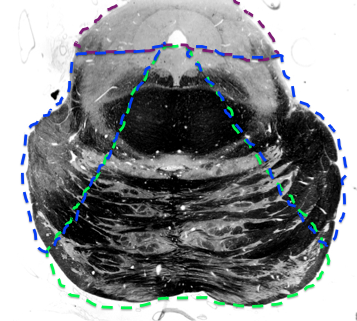

What supplies blood to the pons?

What features in the pons do the (paramedian) basilar branches supply blood to?

What features in the pons do the superior cerebellar artery supply blood to?

trochlear nerve

superior cerebellar peduncle

locus coeruleus

mesecenphalic trigem n.

some medial lemniscus

ALS

What features in the pons does AICA supply blood to?

middle cerebellar peduncle

AICA

lateral part of middle pons until the rostral pons section

purple

superior cerebellar artery

supplies the superior cerebellar peduncle area throughout the pons